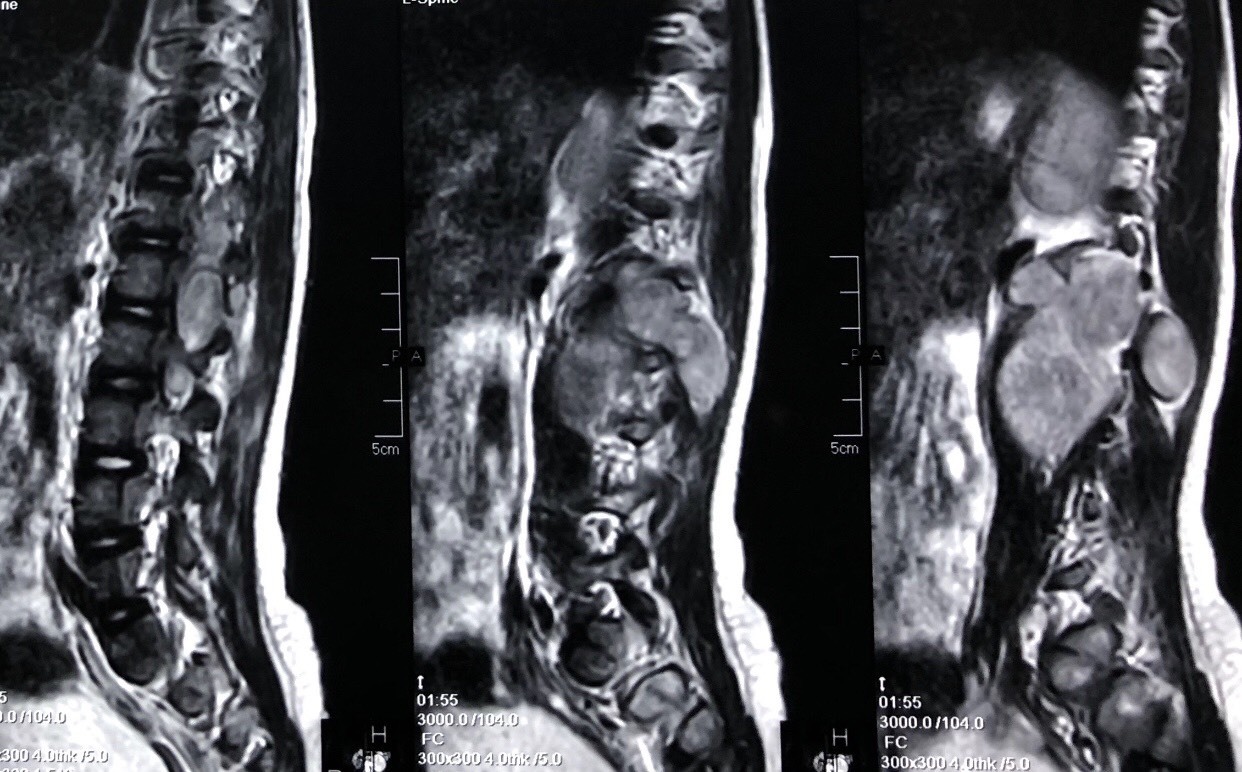

| Khối u chèn ép gây biến dạng cột sống bệnh nhi |

Không từ bỏ hy vọng, tháng 9/2018, qua lời giới thiệu, gia đình đưa bé Khanh đến BV K thăm khám. Trực tiếp điều trị cho bệnh nhi, TS Nguyễn Đức Liên, Trưởng khoa Ngoại thần kinh, BV K chia sẻ, thời điểm nhập viện, bệnh nhi bị khối u xâm lấn mặt trước tủy sống, lan toả 3 đốt sống từ cột sống ngực đến thắt lưng và phát triển vào trong ổ bụng.